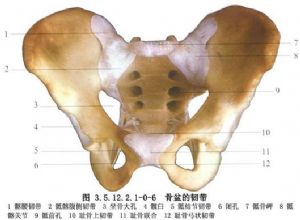

骨盆是由骶骨、尾骨和兩側髖骨(髂骨、坐骨和恥骨)連接而成的堅強骨環。兩側髂骨和骶骨構成骶髂關節。骨盆是脊柱與下肢間的橋樑,軀幹的重力通過骨盆傳遞到下肢,下肢的震盪也通過骨盆上達脊柱。骨盆並保護着盆腔內的重要臟器。

骨盆環分前後兩部分:後部是承重主弓,直立位時重力線經骶髂關節至兩側髖關節爲骶股弓(圖3.5.12.2.1-0-1);坐位時重力線經骶髂關節至兩側坐骨結節爲骶坐弓(圖3.5.12.2.1-0-2~3.5.12.2.1-0-7)。骨盆內血管十分豐富,盆壁動靜脈支緊貼盆壁而行並相互吻合成環。盆腔臟器有伴其動脈的靜脈支和異常豐富的靜脈叢(圖3.5.12.2.1-0-8,3.5.12.2.1-0-9)。後者又多圍繞盆腔內壁,且相互通連。骨盆骨折時易使鄰近的血管損傷而引起大出血,除形成盆腔血腫外,出血量大者還將沿腹膜後間隙向上擴展,形成巨大的腹膜後血腫,引起腹膜刺激症狀。此外,骨盆主要由松質骨構成,血液供應很豐富,骨折斷面可大量滲血,骨盆後壁骨折和骨盆的多發骨折尤易併發大量出血。